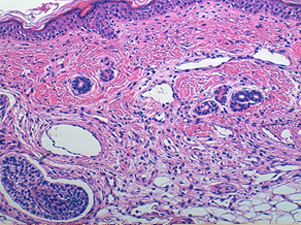

Se realizó biopsia cutánea de una lesión macular de miembro inferior izquierdo. Fue procesada de manera rutinaria y teñida con hematoxilina-eosina donde muestra un aumento del número y tamaño de capilares y vénulas en dermis e hipodermis (Figuras 3 y 4), hallazgo compatible con CMTC.

Figura 3. Tinción de la muestra con hematoxilina-eosina donde se observa un aumento del número y tamaño de capilares y vénulas en dermis e hipodermis.

Los hallazgos histopatológicos son inespecíficos y poco útiles en el diagnóstico diferencial. Las características más comúnmente objetivadas son la dilatación de capilares y vénulas en la dermis3,4,13,15,16 lo que la hace indistinguible de otras malformaciones vasculares.